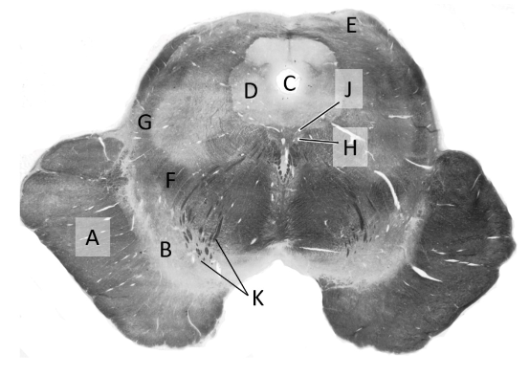

at what level is this?

mid-medulla

what is a?

inferior cerebellar peduncle

what is b?

medial lemniscus

what is c?

pyramidal tract

what is d?

inferior olivary nucleus (m)

what is e?

hypoglossal nerve fibres

what is f?

inferior vestibular nucleus

what is g?

medial vestibular nucleus

what is h?

dorsal nucleus of vagus

what is J?

median longitudinal fasciculus

what is k?

hypoglossal nucleus

what is L?

olivocerebellar fibres

what is m?

olive

what is n?

4th ventricle (m)

what is o?

solitary tract